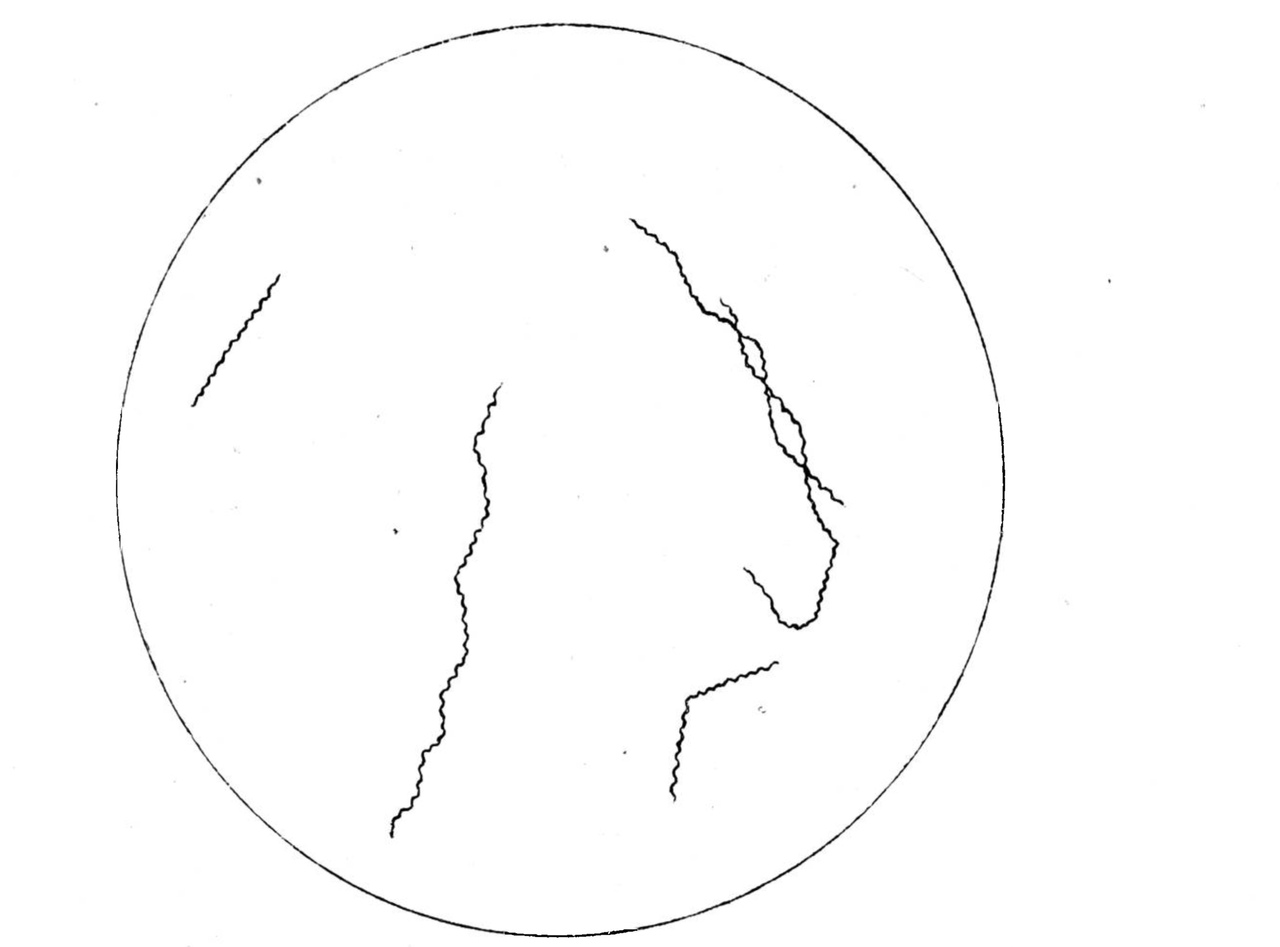

Исходя из этих соображений, я прежде всего попробовал заменить „свежую" ткань и „свежий" кровяной сгусток более индифферентным с химической точки зрения веществом—свернутым белком куриного яйца. Куриное яйцо, лишь-бы оно не обладало явными признаками порчи, варится обычным образом ввод: „вкрутую", после чего белок тщательно отделяется от желтка и делится ножом на кусочки объемом в 1-2 куб. сайт., которые распределяются по пробиркам. Белка из одного куриного яйца достаточно для заполнения 12—15 пробирок. Затем в пробирки прибавляется по 8 куб. сайт, физиологического раствора хлористого натрия; в таком виде пробирки стерилизуются в автоклаве при 120º в течение 15 минут. Остается теперь добавить всюду по 4 куб. сайт, не нагретой лошадиной сыворотки, и среда готова для посева. На приготовленной таким образом питательной среде мне удалось получить с первого же раза очень богатую культуру спирох Obermeiera. Достаточно посеять 1—2 капли крови больного, чтобы через несколько дней при температуре 37°C. получить богатую культуру,—когда при рассматривании капли питательной среды пот микроскопом в поле зрения видно 30—40 спирохет, а иногда и больше. Генерации полученных из крови человека спирохет удаются легко, и в настоящее время я имею в лаборатории 19-ю генерацию первого штамма, выкультивированного из крови больного два месяца тому назад. Развитие культуры идет быстрее, чем это описывают Nogouchi и Hata. Обычно maximum роста достигается па 4—5 день. В культуре можно видеть формы спирохет, отличающиеся по длине и взаимному расположению: наряду с очень короткими спирохетами встречаются экземпляры, по крайней мере в 10 раз превышающие их по длине; большею частью спирохеты располагаются отдельно одна от другой, но вместе с тем можно видеть и аггломерати спирохет, состоящие из 5—6 особей, образующих очень красивые фигуры звезд с расходящимися в разные стороны лучами; иногда можно бывает отметить, как две спирохеты, большею частью длинные, перевиваются, переплетаются одна вокруг другой подлиннику; встречаются, наконец, фигуры, которые проще всего трактовать, как явление поперечного деления спирохет, и которые характеризуются тем, что две спирохеты, большею настаю короткие и находящиеся в оживленном движении, соединены между собою тоненьким, едва заметным мостиком, имеющим вид очень нежной нити. Нужно отметить, что в зависимости от периода развития спирохет в культуре преобладают те или другие формы. Длинные спирохеты, звездообразные фигуры и перевивающиеся формы появляются в культуре в первые дни роста: наоборот, для периода maximum'a роста является характерным как- бы наводнение культуры мелкими формами спирохет, прядающими картине однообразный вид. (См. прилагаемые рисунки).

Приложение к статье В. М. Аристовского.

По культировании спирохеты Obermeier’a“ Культура спирохеты Obermeier’a на среде с куриным белком.

Рис. 1. 24-х часовая культура.

Рис. 2. 2-х суточная культура.